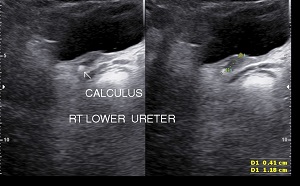

Upper ureteric & lower ureteric calculi can be visualized by sonography however middle ureteric calculus may not be visualized due to overlying gas shadows.

• Ureteric Calculi: